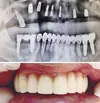

Implant tedavisi